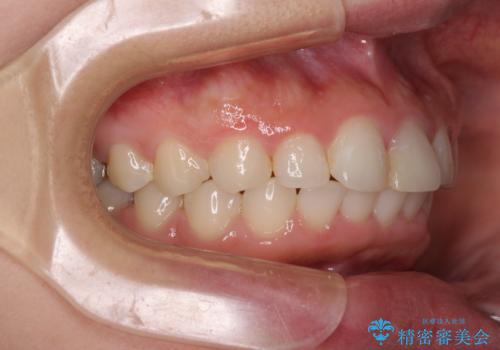

矯正治療の後戻り ガタガタになった前歯の部分矯正

- 以前の矯正治療の後戻りを気にして来院された患者様です。

下顎前歯にデコボコがあるため、ワイヤー矯正により改善することとしました。

もう少しデコボコを改善したかったのですが、ご本人の希望もあり、装置を除去しました。

後戻りを防止するため、舌側を細いワイヤーによる保定を行いました。